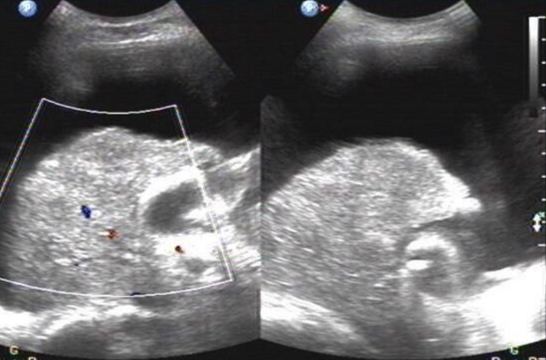

(7)符合影响诊断学。如超声显示:肝区近场弥漫性点状高回声(肝区回声密集增强),远场(或后方)回声衰减。

(4)其首选检查是超声,其超声表现和非酒精性肝病极其相似。确诊的方法用肝穿刺活组织检查。